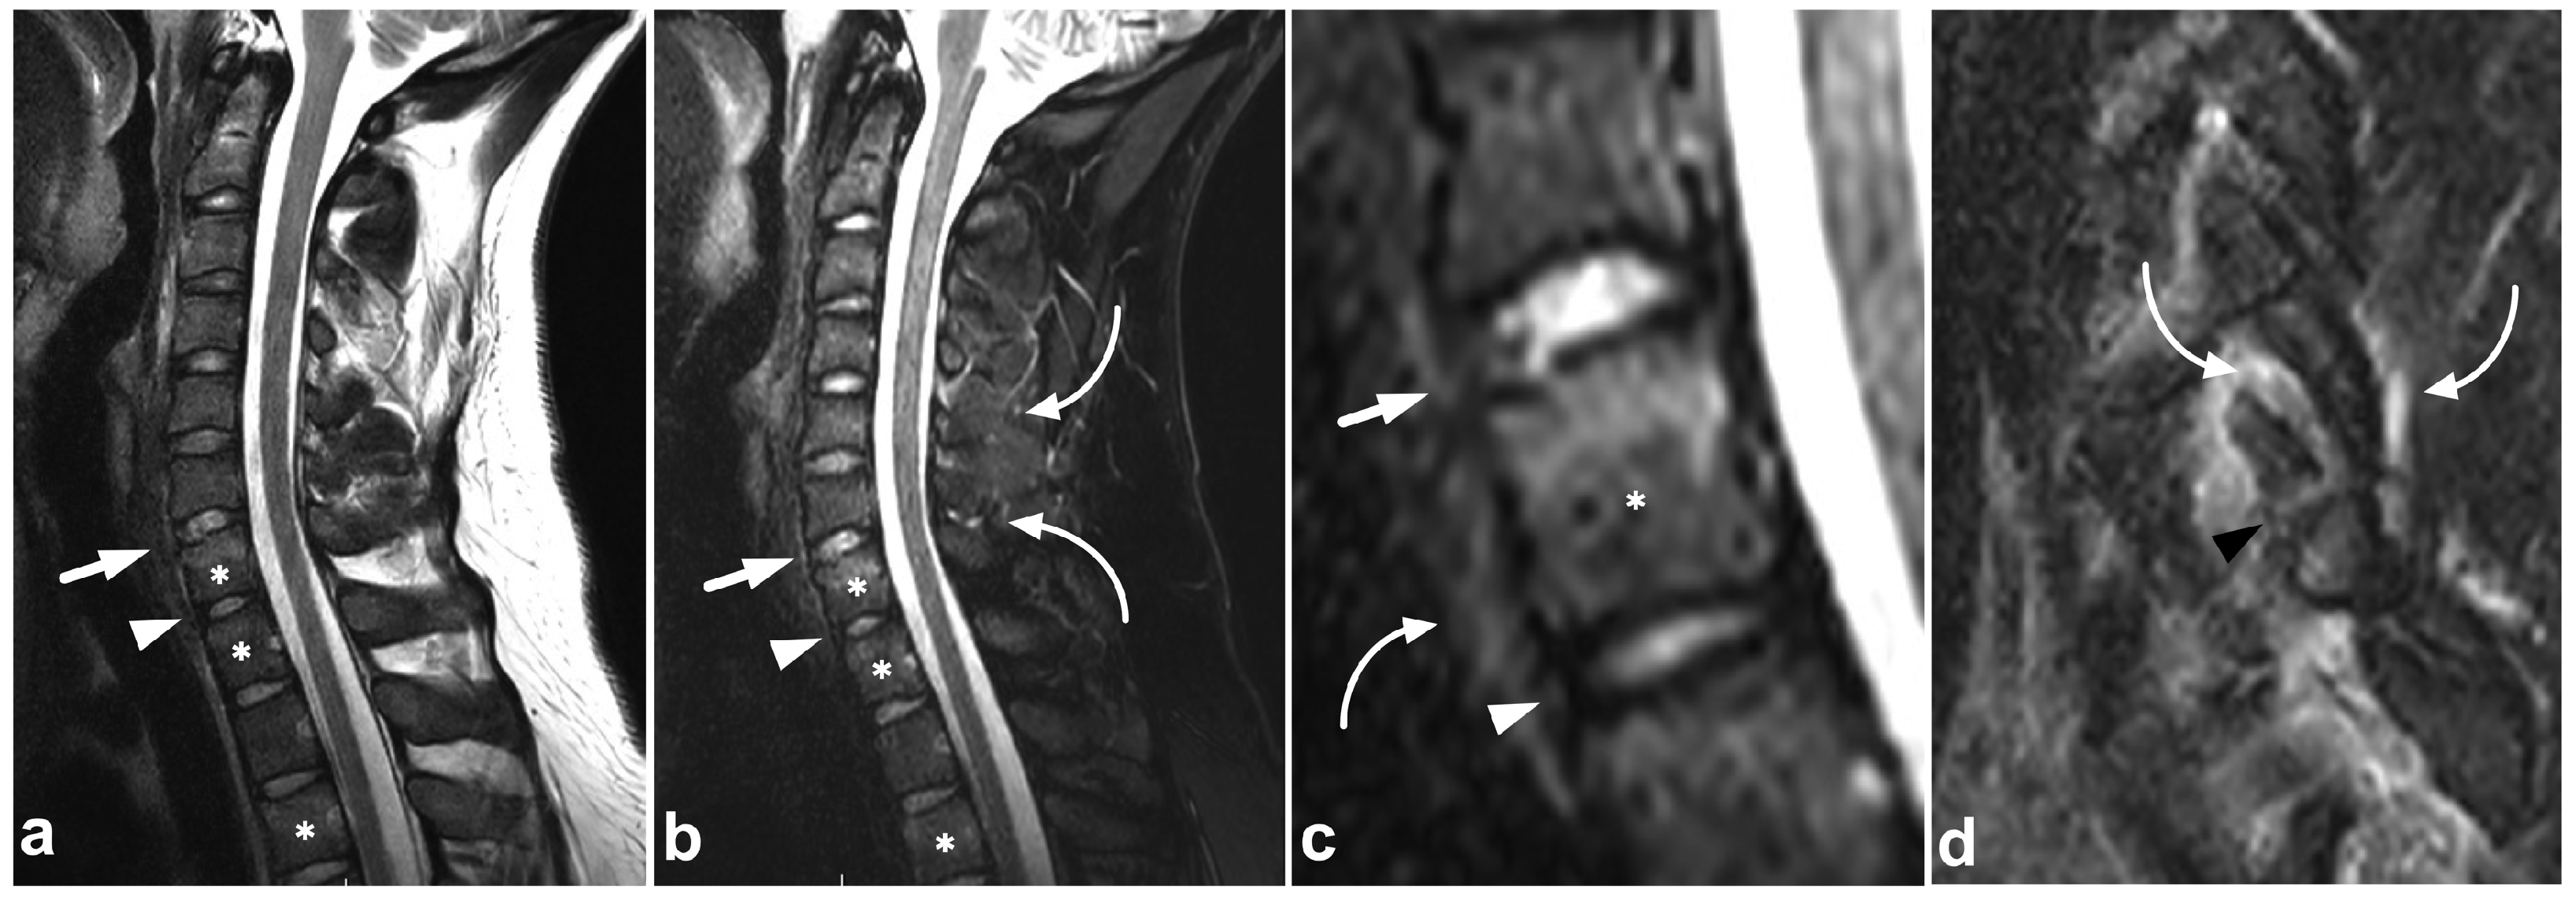

4. Ligamentous Injuries

4.1. Occipitocervical and Atlantoaxial Ligaments

4.2. Posterior Ligament Complex

4.3. Anterior and Posterior Longitudinal Ligaments